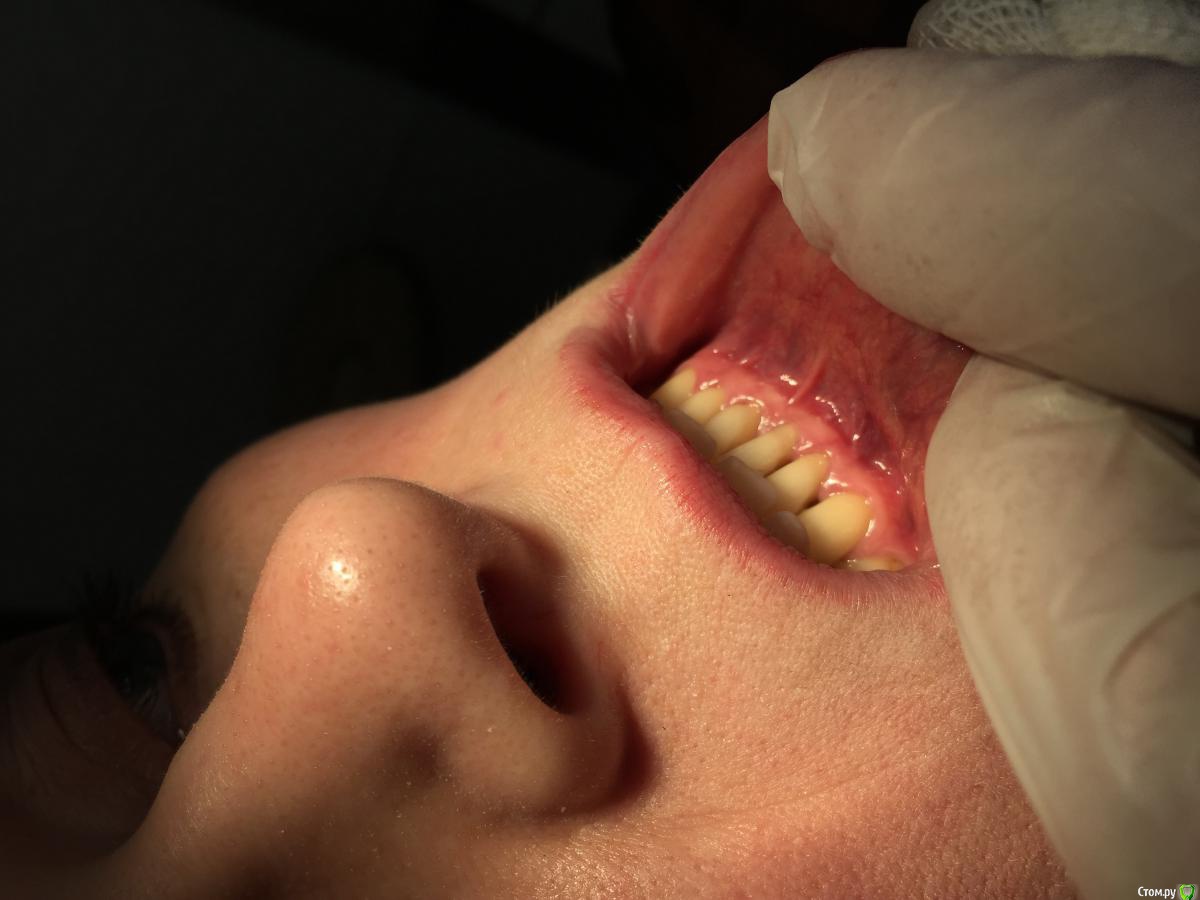

Dr.Safiullin Опубликовано 12 мая, 2017 Поделиться Опубликовано 12 мая, 2017 (изменено) Добрый вечер всем, решил тоже свой первый, небольшой кейс выложитьСильно не ругайте, полгода как получил диплом) Вопрос: 1)Нужно ли подшивать губу? Я не подшил, потому что в гос. времени мало на приём, да и испугался надкостницу травмировать лишний раз. А то боялся получить рубец, хотя не получил его!) 2) на 5 фотке это десквамация? Приветствуются конструктивная критика! Спасибо Изменено 12 мая, 2017 пользователем Dr.Safiullin Ссылка на комментарий

Dr.Safiullin Опубликовано 13 мая, 2017 Автор Поделиться Опубликовано 13 мая, 2017 Доктор, вы прекрасно провели ненужную и бесполезную операцию )) Тут не было показаний для вестибулопластики.Может быть, но а как же преддверие 1.5-2мм, тонкий биотип десны, рецессия по 3 классу по Миллеру в области фронтальных зубов? Из за скученность тоже убыль, но все же. Вот тут может быть информативнее будет Ссылка на комментарий

Bier Опубликовано 13 мая, 2017 Поделиться Опубликовано 13 мая, 2017 у зубов по 2мм кератинизированной десны. Причина не в ее дефиците. Преддверие было нормальным. Ссылка на комментарий